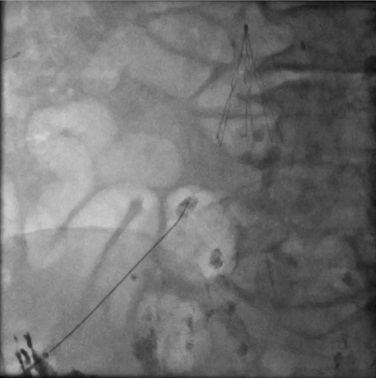

在透视引导下,用21g千叶穿刺乳糜池。 将0.018英寸导丝导入胸导管中,然后插入2.0Fr 微导管沿导丝前进。

乳糜胸淋巴造影